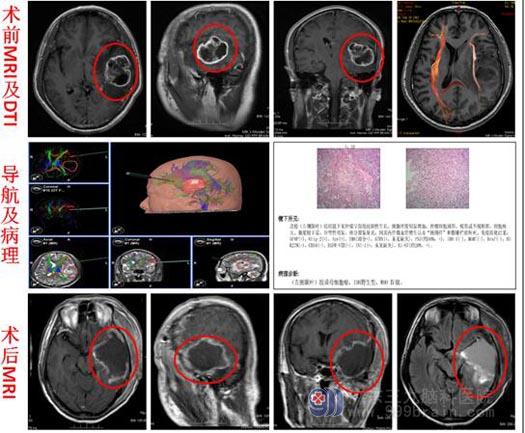

左颞叶胶质母细胞瘤

在广东三九脑科医院头颅MRI检查,显示:1.左侧颞叶占位性病变,大小约为4.1cm×4.9cm×4.0cm,考虑偏高级别肿瘤性病变并卒中,胶质母细胞瘤可能;2.颅内脑膜强化,待排肿瘤脑脊液种植转移可能;3.考虑右侧顶部蛛网膜囊肿。

在患者及家属的积极要求下,由鲁明副院长主刀,在唤醒麻醉下行“左侧颞叶占位病变切除术”,术前导航定位肿瘤边界及标记,术中见皮层下灰白色肿瘤组织,取部分肿瘤组织送快速冰冻:高级别胶质瘤。边切除肿瘤边与患者沟通,查看患者言语及肢体运动情况,予显微镜下分块切除,手术历时7个小时,过程顺利。术后病理:胶质母细胞瘤,WHO IV级。